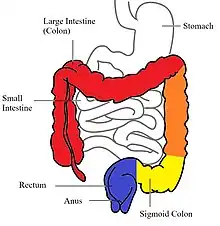

In contrast to Crohn's disease, which can affect areas of the gastrointestinal tract outside of the colon, ulcerative colitis is usually confined to the colon. Inflammation in ulcerative colitis is usually continuous, typically involving the rectum, with involvement extending proximally (to sigmoid colon, ascending colon, etc.).[19] In contrast, inflammation with Crohn's disease is often patchy, with so-called "skip lesions" (intermittent regions of inflamed bowel).[20]

The disease is classified by the extent of involvement, depending on how far the disease extends:[14] proctitis (rectal inflammation), left sided colitis (inflammation extending to descending colon), and extensive colitis (inflammation proximal to the descending colon).[19] Proctosigmoiditis describes inflammation of the rectum and sigmoid colon. Pancolitis describes involvement of the entire colon, extending from the rectum to the cecum. While usually associated with Crohn's disease, ileitis (inflammation of the ileum) also occurs in UC. About 17% of individuals with UC have ileitis.[21] Ileitis more commonly occurs in the setting of pancolitis (occurring in 20% of cases of pancolitis),[12] and tends to correlate with the activity of colitis. This so-called "backwash ileitis" can occur in 10–20% of people with pancolitis and is believed to be of little clinical significance.[22]